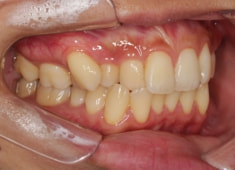

治療前